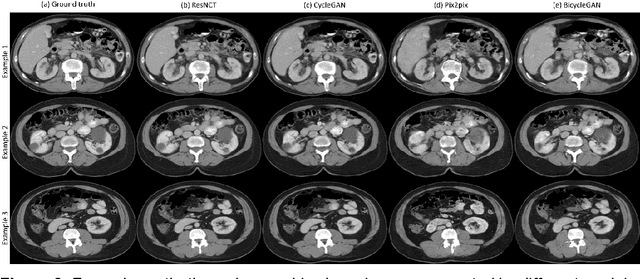

Abstract:Purpose: To develop and evaluate a transformer-based deep learning model for the synthesis of nephrographic phase images in CT urography (CTU) examinations from the unenhanced and urographic phases. Materials and Methods: This retrospective study was approved by the local Institutional Review Board. A dataset of 119 patients (mean $\pm$ SD age, 65 $\pm$ 12 years; 75/44 males/females) with three-phase CT urography studies was curated for deep learning model development. The three phases for each patient were aligned with an affine registration algorithm. A custom model, coined Residual transformer model for Nephrographic phase CT image synthesis (ResNCT), was developed and implemented with paired inputs of non-contrast and urographic sets of images trained to produce the nephrographic phase images, that were compared with the corresponding ground truth nephrographic phase images. The synthesized images were evaluated with multiple performance metrics, including peak signal to noise ratio (PSNR), structural similarity index (SSIM), normalized cross correlation coefficient (NCC), mean absolute error (MAE), and root mean squared error (RMSE). Results: The ResNCT model successfully generated synthetic nephrographic images from non-contrast and urographic image inputs. With respect to ground truth nephrographic phase images, the images synthesized by the model achieved high PSNR (27.8 $\pm$ 2.7 dB), SSIM (0.88 $\pm$ 0.05), and NCC (0.98 $\pm$ 0.02), and low MAE (0.02 $\pm$ 0.005) and RMSE (0.042 $\pm$ 0.016). Conclusion: The ResNCT model synthesized nephrographic phase CT images with high similarity to ground truth images. The ResNCT model provides a means of eliminating the acquisition of the nephrographic phase with a resultant 33% reduction in radiation dose for CTU examinations.